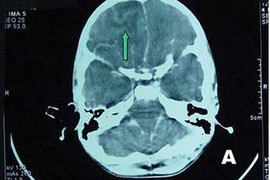

(VTC News) - Trung tâm Pháp y TP.HCM xác nhận, có trường hợp một cháu trai 6 tuổi ở ngụ tại quận Bình Thạnh, TP.HCM tử vong có khối áp xe trong đầu.